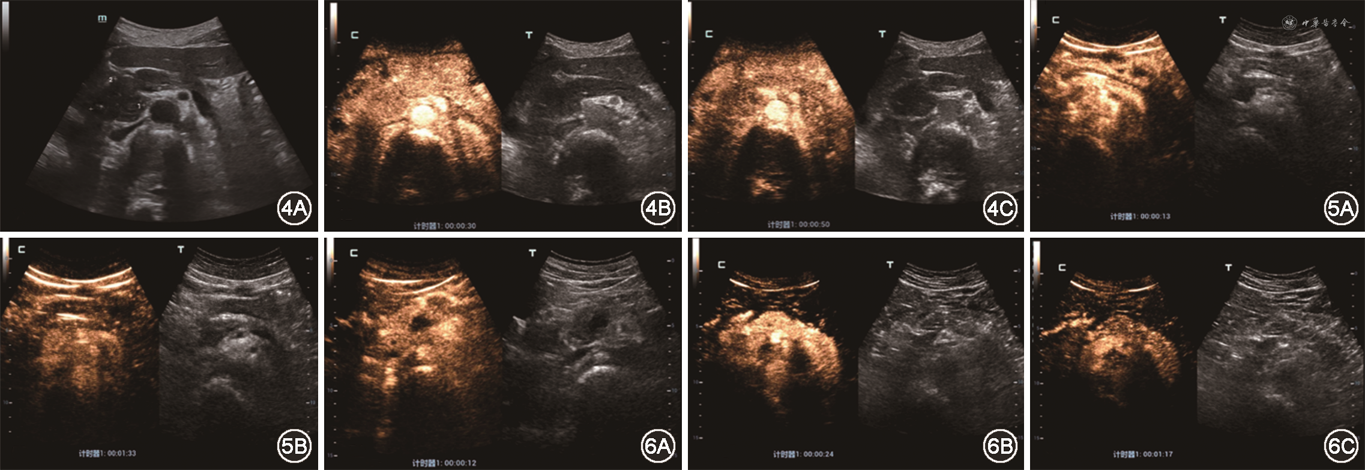

3. 治疗前首次就诊时胰腺超声造影表现:(1)17例胰腺弥漫性受累者中,有9例胰腺整体在增强早期、增强晚期、延迟期依次表现为稍低增强-低增强-低增强(图1),有5例在增强早期、增强晚期、延迟期依次表现为等增强-低增强-低增强(图2),有3例在增强早期、增强晚期、延迟期依次表现为稍高增强-低增强-低增强;(2)37例胰腺局灶性受累者中,有25例病灶在增强早期、增强晚期、延迟期均表现为低增强-低增强-低增强(图3),7例在增强早期、增强晚期、延迟期均表现为等增强-等增强-等增强(图4),2例在增强早期、增强晚期、延迟期依次表现为稍高增强-低增强-低增强,3例在增强早期、增强晚期、延迟期依次表现为稍高增强-等增强-等增强。

17例胰腺弥漫性受累者中:(1)共有8例患者治疗后在增强早期-增强晚期-延迟期3期中至少有1期出现了造影强度的增高:其中有5例患者胰腺整体的增强模式由治疗前的稍低增强-低增强-低增强变为治疗后的高增强-稍低增强-稍低增强(图5),2例由治疗前的稍低增强-低增强-低增强变为治疗后的等增强-低增强-低增强,1例由治疗前的等增强-低增强-低增强变为治疗后的等增强-等增强-等增强;(2)共有2例患者在治疗后出现了造影强度的减低:由治疗前的稍低增强-低增强-低增强变为治疗后的低增强-低增强-低增强;(3)共有7例患者在治疗前后造影强度没有发生变化,其中有4例在治疗前后均表现为等增强-低增强-低增强,3例在治疗前后均表现为稍高增强-低增强-低增强。

37例胰腺局灶性受累者中:(1)共有21例患者治疗后在增强早期-增强晚期-延迟期3期中至少有1期出现了造影强度的增高,其中有15例患者由治疗前的低增强-低增强-低增强变为治疗后的等增强-等增强-等增强(图6),4例由治疗前的低增强-低增强-低增强变为治疗后的高增强-低增强-低增强,1例由治疗前的稍高增强-低增强-低增强变为治疗后的稍高增强-稍低增强-稍低增强,1例由治疗前的稍高增强-低增强-低增强变为治疗后的稍高增强-等增强-等增强;(2)共有16例患者治疗前后在造影强度上没有发生变化,其中有6例在治疗前后均表现为低增强-低增强-低增强,7例在治疗前后均表现为等增强-等增强-等增强,3例在治疗前后均表现为稍高增强-等增强-等增强。